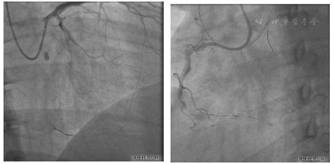

送入IVUS导管至PL,回撤检查:IVUS导管均位于血管腔内(图15A~E),PL可见约200°钙化(图15A),PL近段至右冠状动脉远段可见内膜下血肿(图15B~D),右冠状动脉中段可见斑块浸润,无血肿(图15E)。应用Quantum 2.5 mm×15 mm再次自PL近段扩张病变(图16)。

右冠状动脉置入4枚支架:RSINT 2.25 mm×30.00 mm、Firebird 2.75 mm×33.00 mm、Firebird 3.5 mm×33.0 mm、Firebird 4.0 mm×29.0 mm(图17),应用非顺应性球囊扩张支架(图18)。

造影评价右冠状动脉支架置入后效果及评价左冠状动脉血管情况(图19)。

手术耗时238 min,应用优维显470 ml,术中每30分钟监测ACT 1次,维持ACT在300~350 s之间,术中累计应用肝素16 000 IU。术后病情稳定,心脏超声未提示心包积液。术后第3天康复出院。